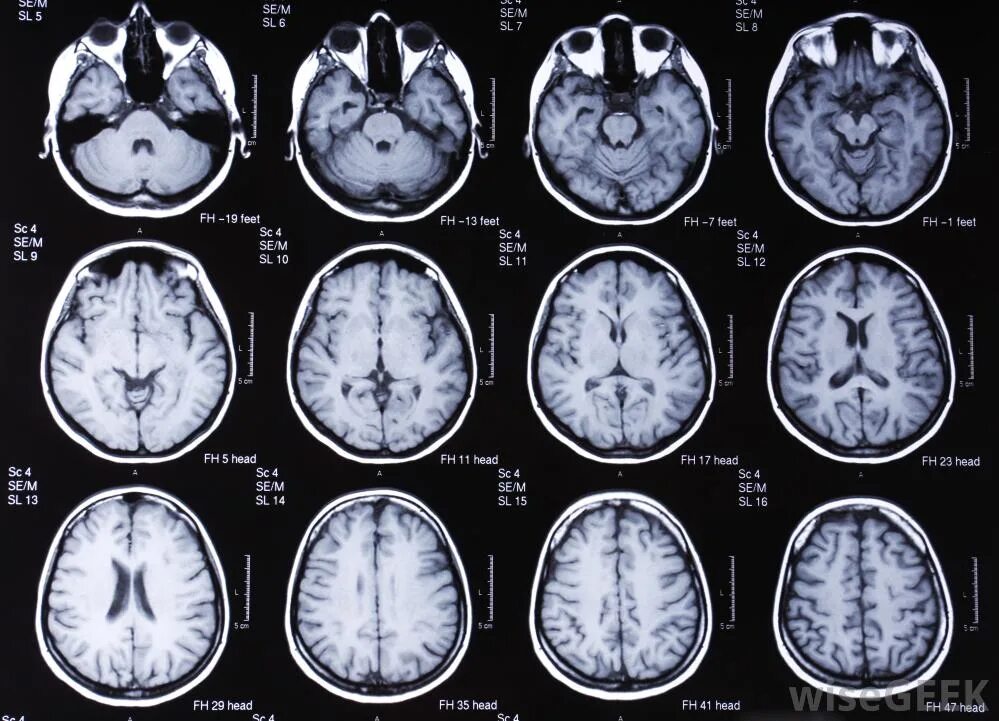

Что можно увидеть на мрт